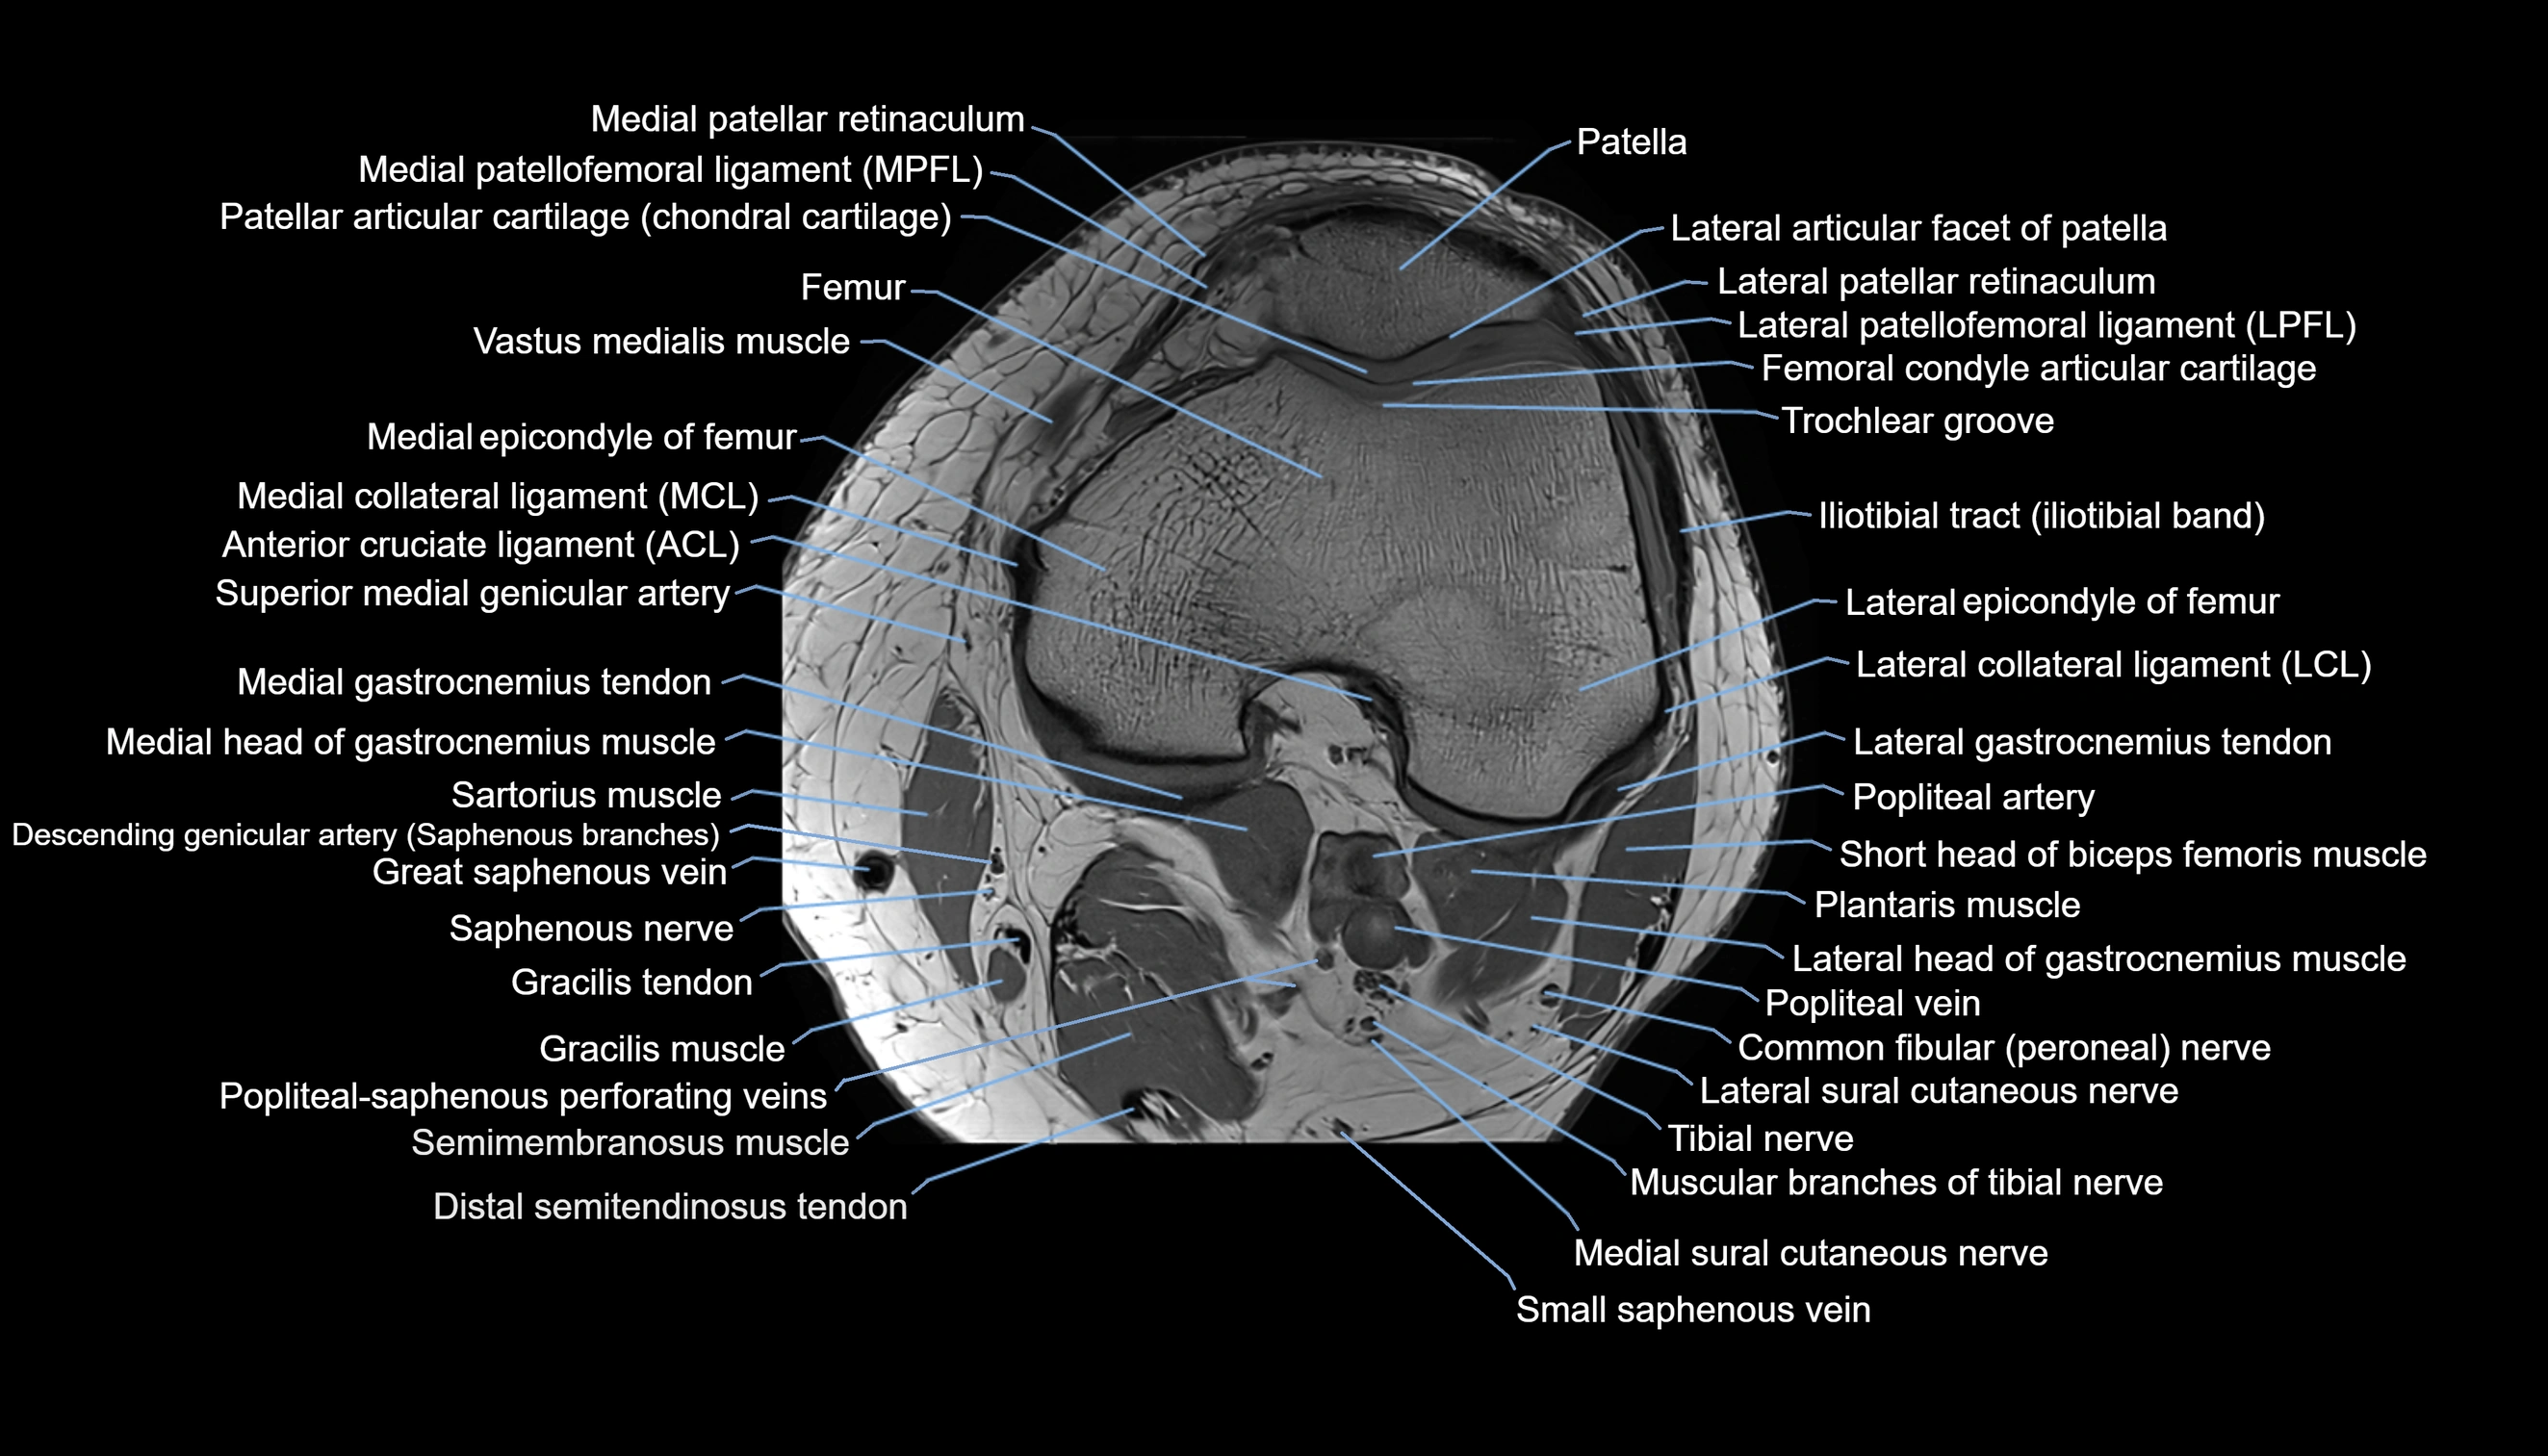

- Femoral condyle articular cartilage

- Lateral collateral ligament

- Lateral epicondyle of femur

- Lateral gastrocnemius tendon

- Lateral head of gastrocnemius muscle

- Lateral patellofemoral ligament

- Medial collateral ligament

- Medial epicondyle of femur

- Medial gastrocnemius tendon

- Medial head of gastrocnemius muscle

- Medial patellar retinaculum

- Medial patellofemoral ligament

- Patella

- Popliteal–Saphenous perforating veins

- Small saphenous vein

- Trochlear groove